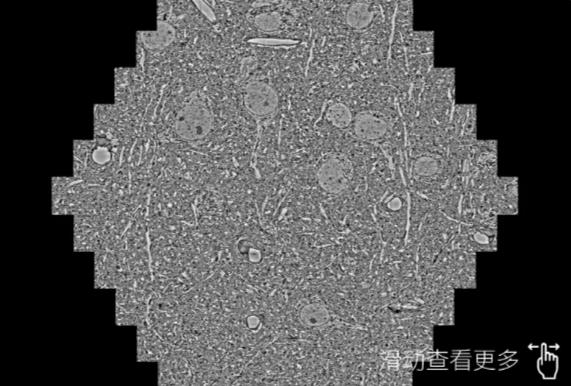

鼠脑切片。左图使用开州蔡司开州扫描电镜MultiSEM706对165μmx143pm面积区域成像,耗时仅需1.5秒。右图为鼠脑切片中30μm区域放大效果。样品由芝加哥大学B.Kasthuri提供。